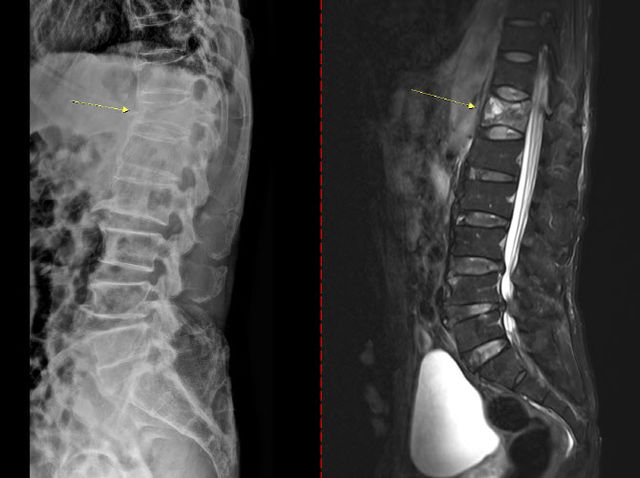

골다공증은 초기 징후가 뚜렷하지 않아 특히 주의해야 한다. 통증이나 자각 증상이 거의 없다가 시간이 지나 가벼운 충격만으로도 손목이나 대퇴골(엉덩이뼈)이 골절되면서 뒤늦게 진단되는 경우도 있다. 때로는 등이 굽거나 키가 줄어드는 척추 압박골절이 나타날 수도 있다. 치료 없이 방치하면 뼈는 점점 약해지고 척추와 손목, 대퇴골 골절 등 중대한 골절이 발생할 수 있다. 특히 대퇴골 골절은 고령 환자에서 수술 후 합병증, 장기 입원, 사망률 증가와 직결되는 중증질환이다. 척추 압박골절의 경우 자세 변화, 만성 통증, 보행 장애를 유발해 ▲활동량 감소 ▲근력 저하 ▲추가 골절의 악순환으로 이어진다.